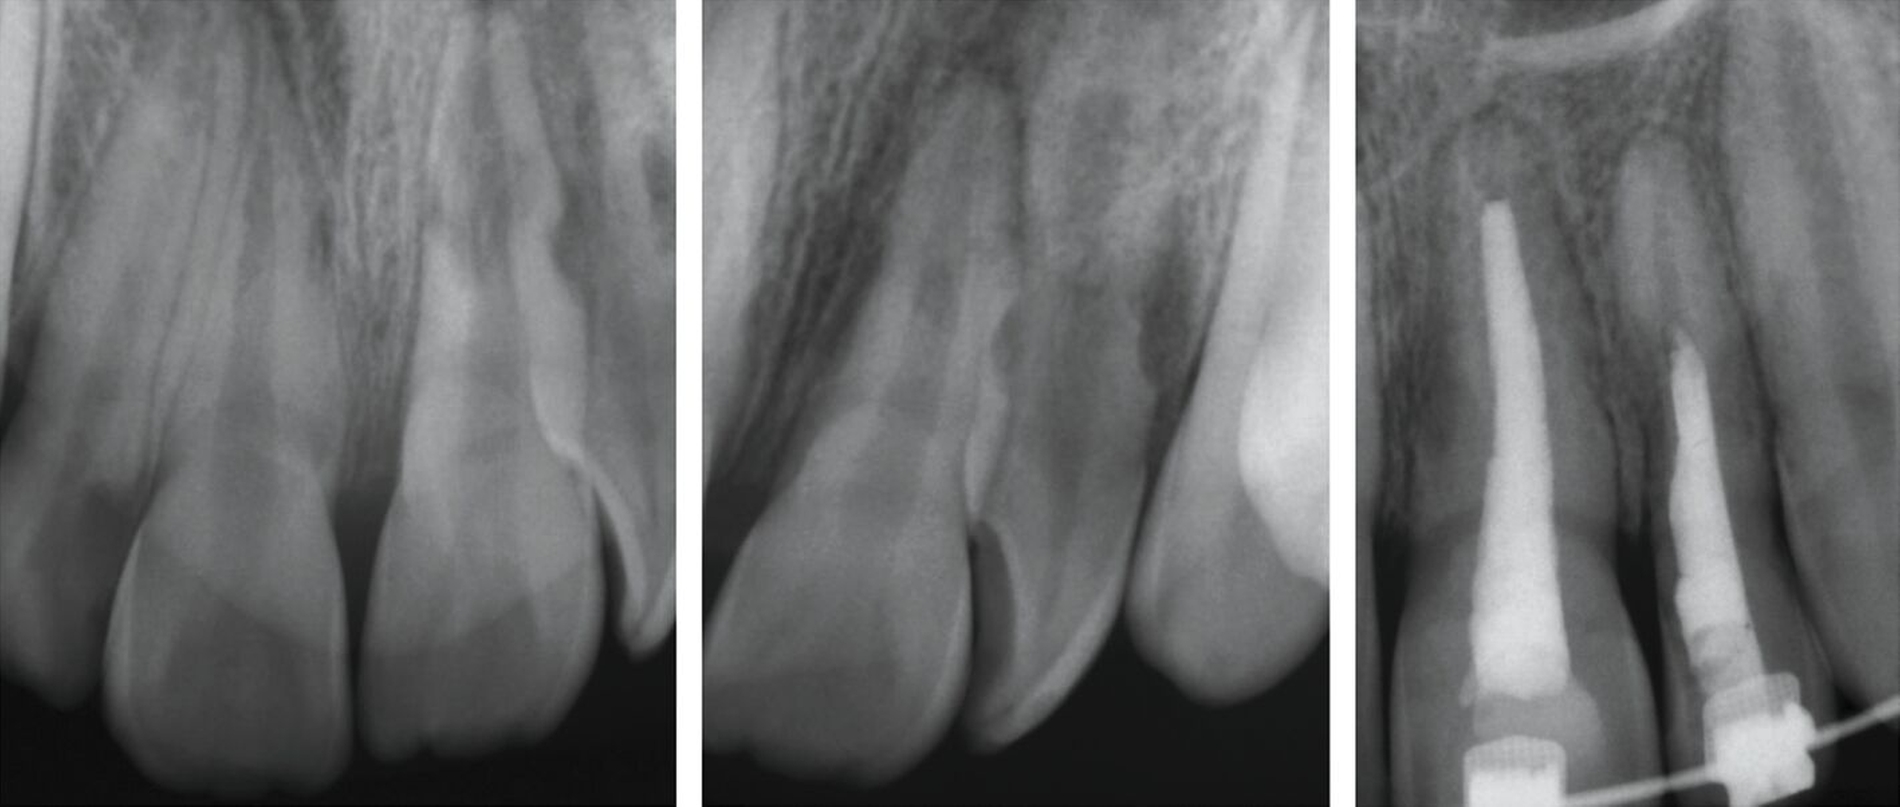

Apikaler Verschluss durch Langzeiteinlage mit Kalziumhydroxid (Apexifikation): Bei Zähnen mit offenem Apex führen Langzeiteinlagen mit Kalziumhydroxid zur Induktion einer apikalen Hartgewebsbarriere, die günstigere Bedingungen für die Applikation einer konventionellen Wurzelkanalfüllung schafft. Hierzu sind raumfüllende Einlagen mit Kalziumhydroxid über mehrere Monate notwendig, wobei das Material in regelmäßigen Intervallen gewechselt wird (Abbildung 6).

Die Behandlung ist vergleichsweise einfach, kann über die gesetzliche Krankenkasse abgerechnet werden und weist eine hohe Erfolgswahrscheinlichkeit in Bezug auf eine periapikale Heilung auf. Problematisch ist allerdings die deutlich erhöhte Gefahr für zervikale Wurzelfrakturen, die abhängig vom Stadium der Wurzelentwicklung zwischen 28 Prozent und 77 Prozent liegt [Cvek, 1992]. Dies ist zum einen auf den negativen Einfluss der Langzeiteinlage auf die mechanischen Eigenschaften des Dentins zurückzuführen, zum anderen auf den Zeitraum von sechs bis 18 Monaten, in dem die dünnen Dentinwände im zervikalen Bereich nicht adhäsiv stabilisiert werden können (Abbildung 6).

Apikaler Verschluss mit hydraulischem Kalziumsilikatzement (apikaler Plug): Diese Therapie hat sich in den vergangenen zwei Jahrzehnten in vielen endodontischen Praxen zum Standardverfahren entwickelt. Hierbei wird nach adäquater Desinfektion des Wurzelkanalsystems ein biokompatibler hydraulischer Kalziumsilikatzement (zum Beispiel MTA) in einer Schichtstärke von circa 4 mm in direktem Kontakt mit den periapikalen Geweben eingebracht. Der restliche Wurzelkanal wird vorzugsweise mit Sealer und erwärmter Guttapercha gefüllt. Der anschließende Verschluss mit Komposit sollte tief genug eingebracht werden, um die zervikalen Kanalbereiche adhäsiv zu stabilisieren und einer Fraktur vorzubeugen (Abbildung 7). Die Erfolgsquoten für den apikalen Verschluss mit MTA liegen nach über vier bis acht Jahren bei über 90 Prozent [Mente et al., 2013; Re und Schwartz, 2017]. Der Nachteil des MTA-Plugs besteht in der erschwerten Entfernbarkeit im Fall einer notwendigen Revision. Die Behandlung ist im Vergleich zur Apexifikation mit Kalziumhydroxid aufwendiger und erfordert optische Vergrößerungshilfen für eine optimale Durchführung.

Revitalisierung: Nach gründlicher Desinfektion des Wurzelkanalsystems wird durch mechanische Provokation des apikalen Gewebes eine Blutung in den Kanal induziert, um mesenchymale Stammzellen aus der apikalen Papille in den Wurzelkanal einzuschwemmen, die neues Hart- und Weichgewebe im Wurzelkanal bilden können [Galler et al., 2016]. Das Blutkoagulum wird im zervikalen Wurzelkanalbereich mit einer Kollagenmatrix und anschließend mit einem hydraulischen Kalziumsilikatzement abgedeckt. Die Zugangskavität wird mit Komposit adhäsiv verschlossen. Die Erfolgsquoten nach Revitalisierung hinsichtlich der Ausheilung periapikaler Entzündungen entsprechen denjenigen nach apikalem Verschluss [Torabinejad et al., 2017]. Darüber hinaus ist eine Stärkung der fragilen Wurzelwände durch Fortschritt des Wurzelwachstums möglich (Abbildung 8), aber nicht sicher vorhersagbar [Kahler et al., 2017]. Eine Revitalisierungsbehandlung kann im Vergleich zur Apexifikation mit Kalziumhydroxid als aufwendiger angesehen werden.